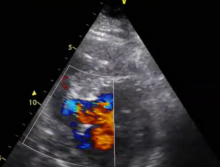

In this video, the authors present an interesting case of postmyocardial infarction VSD which was initially treated surgically with a pericardial patch closure. Subsequently, a patch dehiscence resulted in an intractable heart failure. A septal occlusion device was used, but due to the complexity of the VSD, the device dislodged into the right ventricle and could not be retrieved. The heart team discussion led to the utilization of the authors’ minimal access expertise to access the VSD and perform closure through a right minithoracotomy. The outcome was successful, and there was no flow through the new VSD patch during two years of follow-up. The patient experienced minimal dyspnea of New York Heart Association Classification 0-I and was recently discharged from surgical follow-up.